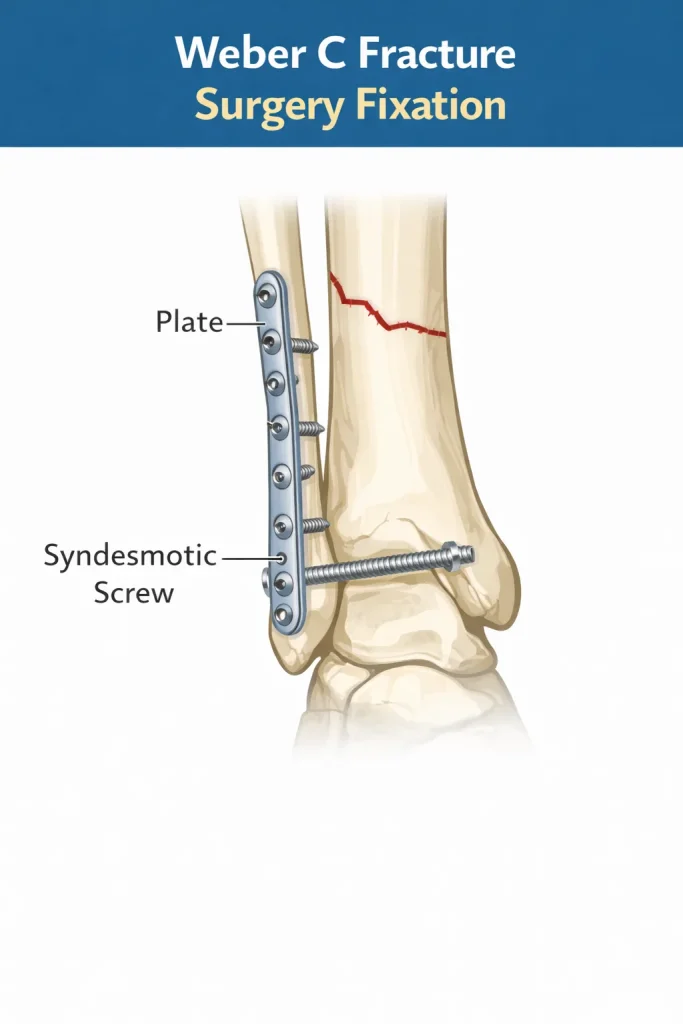

Weber C Fracture

A Weber C fracture occurs above the syndesmosis. These fractures are usually unstable and associated with ligament disruption.

Surgical Management

Most Weber C fractures require:

- Plate fixation of the fibula

- Syndesmotic screw or tightrope fixation

- Restoration of ankle alignment

Because the syndesmosis is disrupted, surgical stabilization is commonly required.

The goal of surgery is to restore the normal relationship between the tibia, fibula, and talus – known as the ankle mortise. When the mortise is not properly restored, long-term outcomes deteriorate significantly.

Surgical steps for Weber C fracture:

- Open reduction of the fibular fracture

- Internal fixation with a plate and screws

- Assessment of syndesmotic stability intraoperatively

- Syndesmotic fixation if instability is confirmed (screw or suture button/tightrope)

- Assessment of the medial side if deltoid ligament is torn